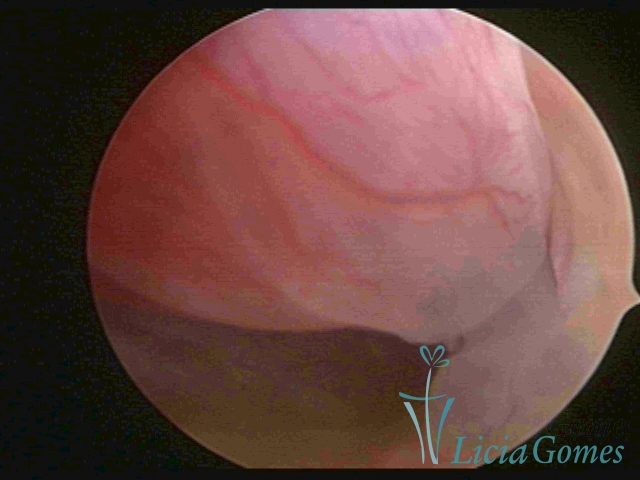

PÓLIPOS ENDOCERVICAIS

São tumores benignos, resultantes da proliferação focal reativa aos processos inflamatórios ou à situações de hiperestrogenismo, e podem ter sésseis (com a base de implantação larga) ou pediculados do epitélio.